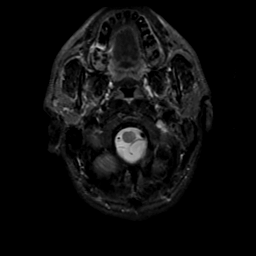

MR Study #20 October 6, 1991 -- Slice #2

[Home][Help][Clinical][Tour 1][Tour 2] Slice 2